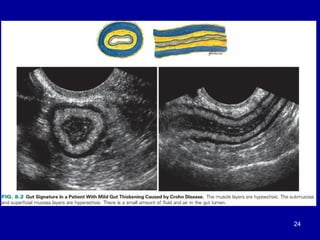

Ultrasound

•Gas content within the gut lumen can make visibility difficult

• allows assessement of content , diameter & motility of GIT

•Ultrasound is superior to both CT & MRI for resolution of the gut wall

layers

•Normal gut is compressible and gas pockets displaced away

from the region of interest

• thickened abnormal bowel loops are non compressible &

remain unchanged

•The normal gut wall is uniform with an average thickness of

3mm if distended & 5mm if not distended

Ultrasound •Gas content withinthe gut lumen can make visibility difficult • allows assessement of content , diameter & motility of GIT •Ultrasound is superior to both CT & MRI for resolution of the gut wall layers •Normal gut is compressible and gas pockets displaced away from the region of interest • thickened abnormal bowel loops are non compressible & remain unchanged •The normal gut wall is uniform with an average thickness of 3mm if distended & 5mm if not distended 21